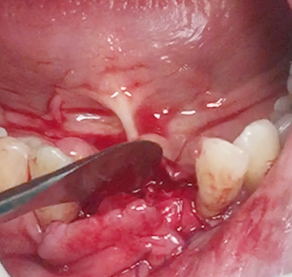

Crown lengthening (Anterior teeth)